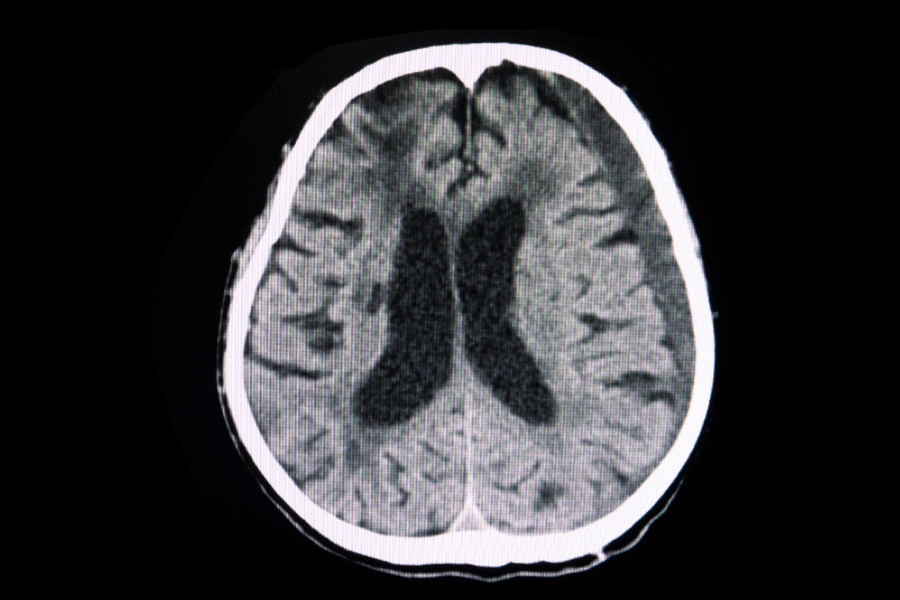

Article originally published in NeuroNews International. The two prevailing techniques used during surgical treatments of traumatic acute subdural haematomas (SDHs)—craniotomy and decompressive craniectomy—have demonstrated broadly similar…